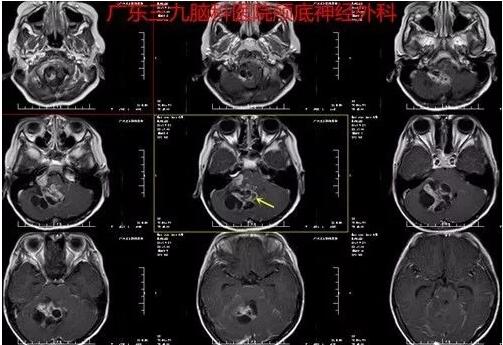

图3:术前MR轴位增强片,增强后病变实性部分和囊壁呈明显异常强化影,范围约为6.0cm×5.1cm×5.6cm,其内示少许流空血管影,周围未见明显水肿影。脑干受,四脑室受压消失。增强后全脑沟内示广泛线状异常强化影。双侧小脑幕增厚、强化。